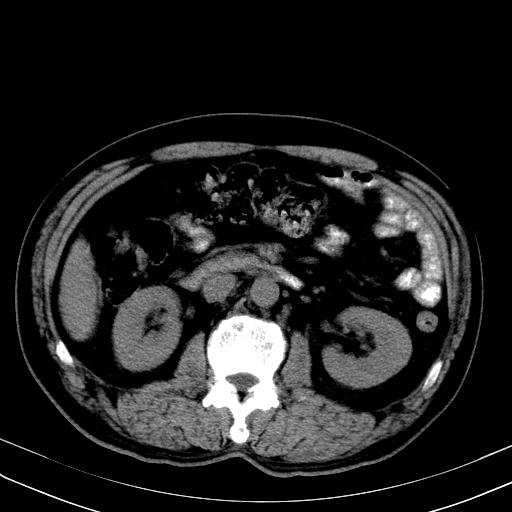

先行ct平扫,纵膈内多发软组织影,ct值约为36hu,以下为增强扫描和腹部平扫。

经典?纵膈多发肿大淋巴结。腹膜后未见异常。

还见胃窦壁增厚!转移亦有可能!

1)考虑淋巴瘤。2)双侧少量胸腔积液。

大家看看肝脏右叶片状低密度影是什么改变啊?

淋巴瘤?肝脏请增强后说啊

多发肿大淋巴结影,肝内改变需结合强化观察

多发肿大淋巴结影,肝内改变需结合强化观察。